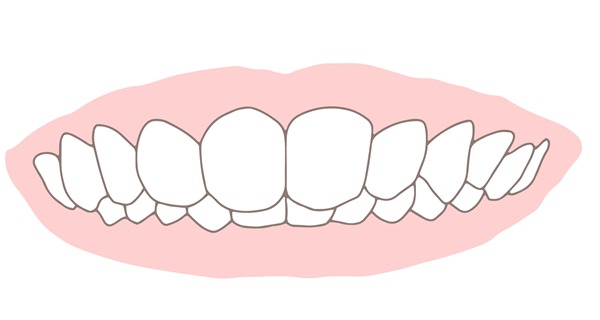

過蓋咬合とは、前歯の噛み合わせが深い状態です。上の前歯が下の前歯を覆い隠し、歯茎が傷ついてしまうこともあります。骨格の位置に異常があったり、舌で歯を押す癖があったりすることなどが原因です。

過蓋咬合は、笑ったときに歯茎がくっきりと見えるガミースマイルの原因にもなりやすく、悩みを抱えている方が少なくありません。

過蓋咬合の方は、上の歯の裏の歯茎に下の歯が当たるため、歯茎に炎症が起こりやすくなります。慢性的な痛みや違和感に悩まされることもあるでしょう。また、前歯の噛み合わせが悪いため、食べ物をうまく噛むことができません。

下顎が動く範囲が狭くなり、顎に負担がかかって顎関節症に発展することがあります。また、過蓋咬合の方はガミースマイルになりやすいことが特徴です。歯茎が見えることがコンプレックスとなり、人前で笑うのをためらってしまう方もいます。